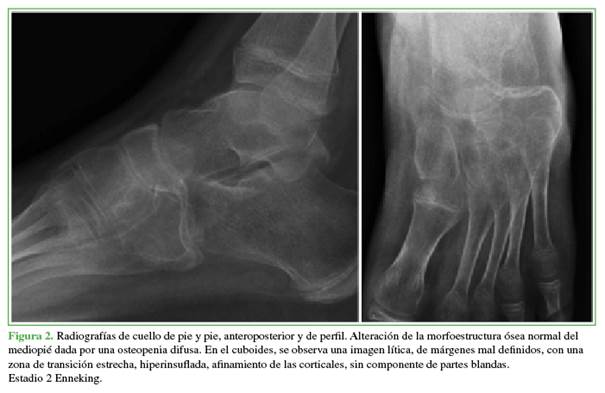

La tumoración estaba situada en la cara externa de mediopié, en el sector del hueso cuboides, medía 3 x 3 cm, y tenía límites mal definidos, forma ovoide, superficie irregular, consistencia pétrea, era inmóvil y dolorosa a la digitopresión, y estaba relacionada con planos profundos (Figuras 1 y 2).

Ante una tumoración que impresionaba de estirpe ósea en un adolescente, se lo evalúo siguiendo el algoritmo clásico de nuestra institución: radiografías de la región afectada, análisis de sangre con relevo infeccioso y resonancia magnética (Figura 3).

La fase evolutiva del QOA se puede clasificar de acuerdo con los estadios de Enneking; en nuestro caso, correspondía a un estadio 2 (activo).